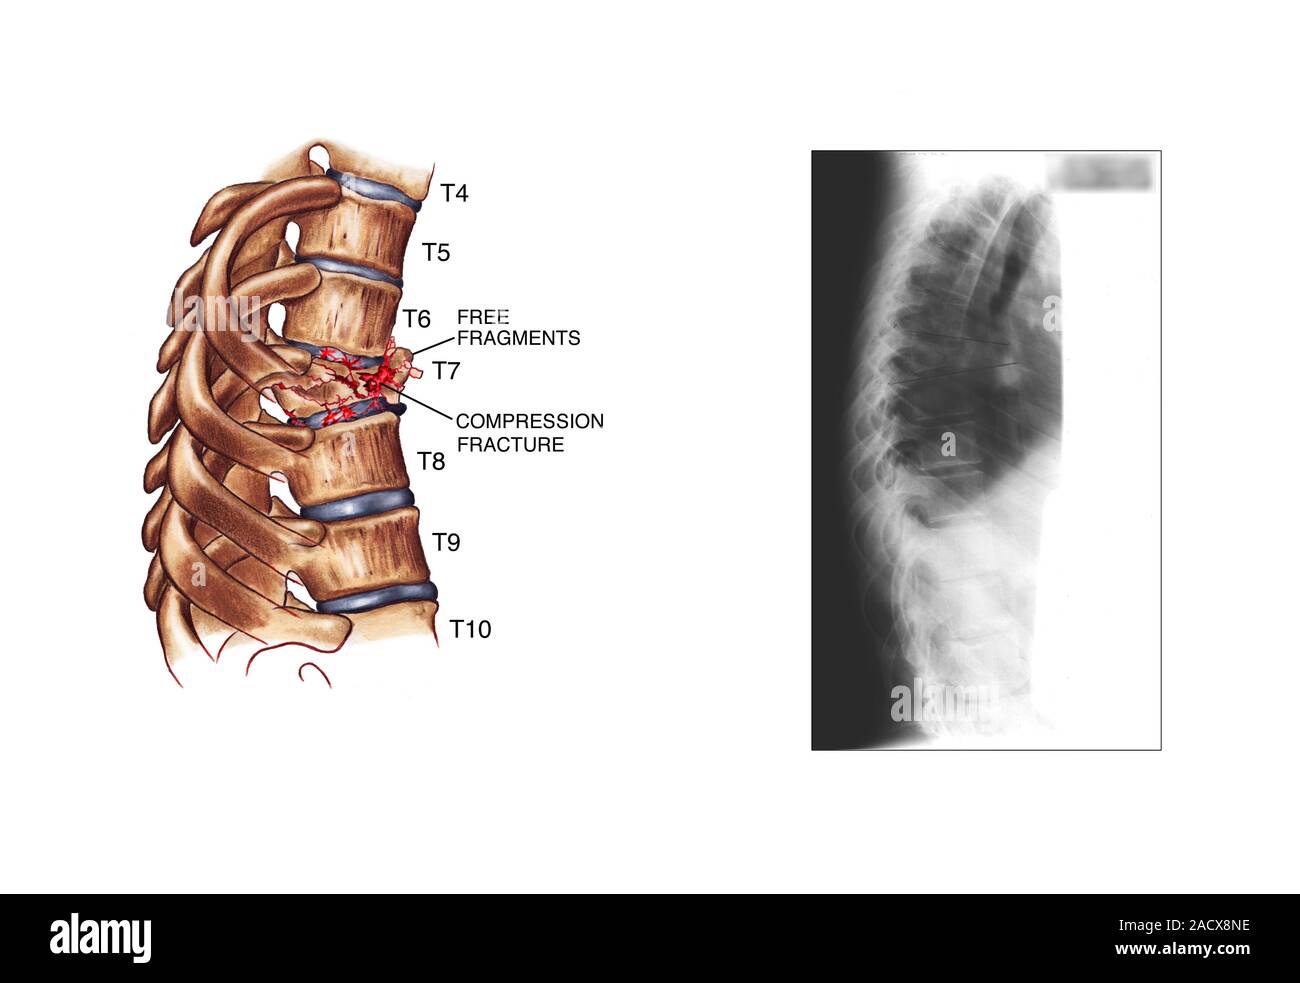

Fractured spine

Fractured spine 140 фотографий